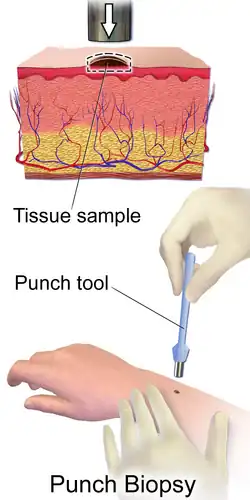

| Diagnostic method | Biopsy[4] |

Although the ideal method of diagnosis of melanoma is complete excisional biopsy,[19] alternative methods may be required based on the location of the melanoma. Dermatoscopy of acral pigmented lesions is very difficult but can be accomplished with diligent focus. Initial confirmation of the suspicion can be done with a small wedge biopsy or small punch biopsy.[4] Thin deep wedge biopsies can heal very well on acral skin, and small punch biopsies may provide enough information to suggest if a lesion is cancerous. Once this confirmatory biopsy is done, a second complete excisional skin biopsy can be performed with a narrow surgical margin (1 mm). This second biopsy will determine the depth and invasiveness of the melanoma,[20] and will help to guide further treatment if necessary. In order to establish the Breslow's depth of the lesion, the most raised section of the pigmented area should be sampled.[21] If the melanoma involves the nail fold or the nail bed, complete excision of the nail unit might be required for accurate sampling.